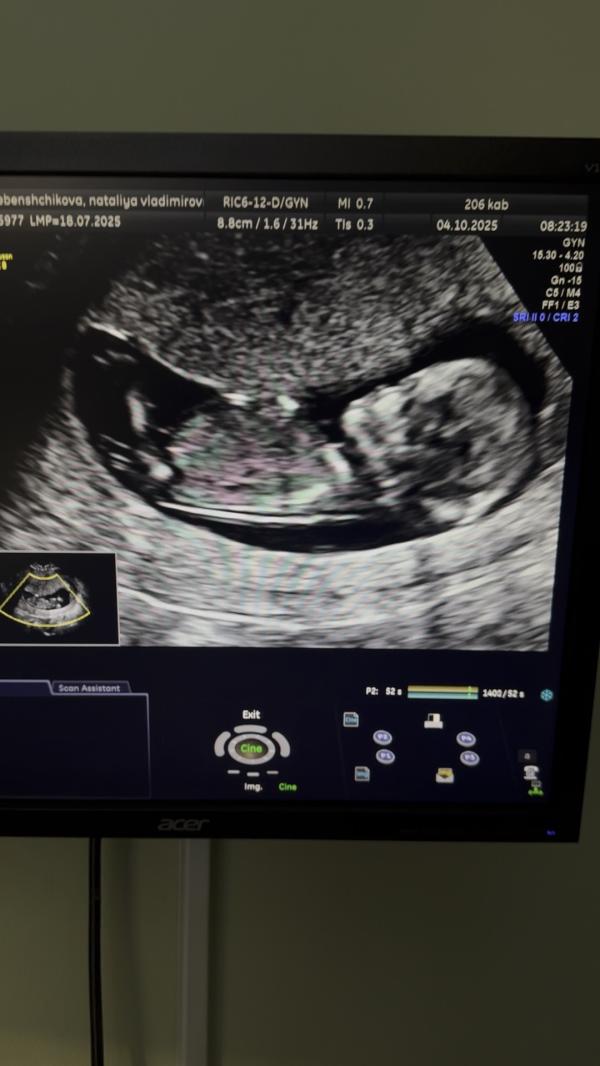

Мне надо восстановить хронологию событий, раз я не стала вести свою страничку с самого начала. УЗИ проходила каждые 2 недели. История развития маленького человека🥰 Последнее фото со скрининга на флотской, лялька с характером, совсем не давалась смотреть и фоткаться😁